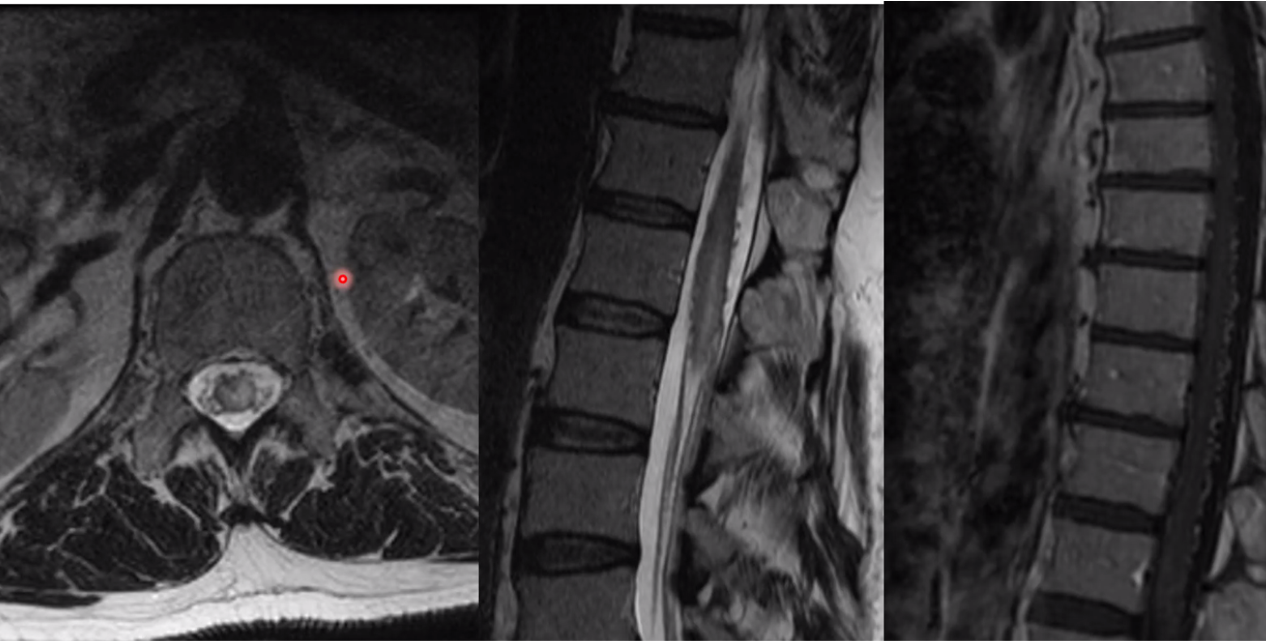

cav mal in the conus medullaris

chocolate covered popcorn